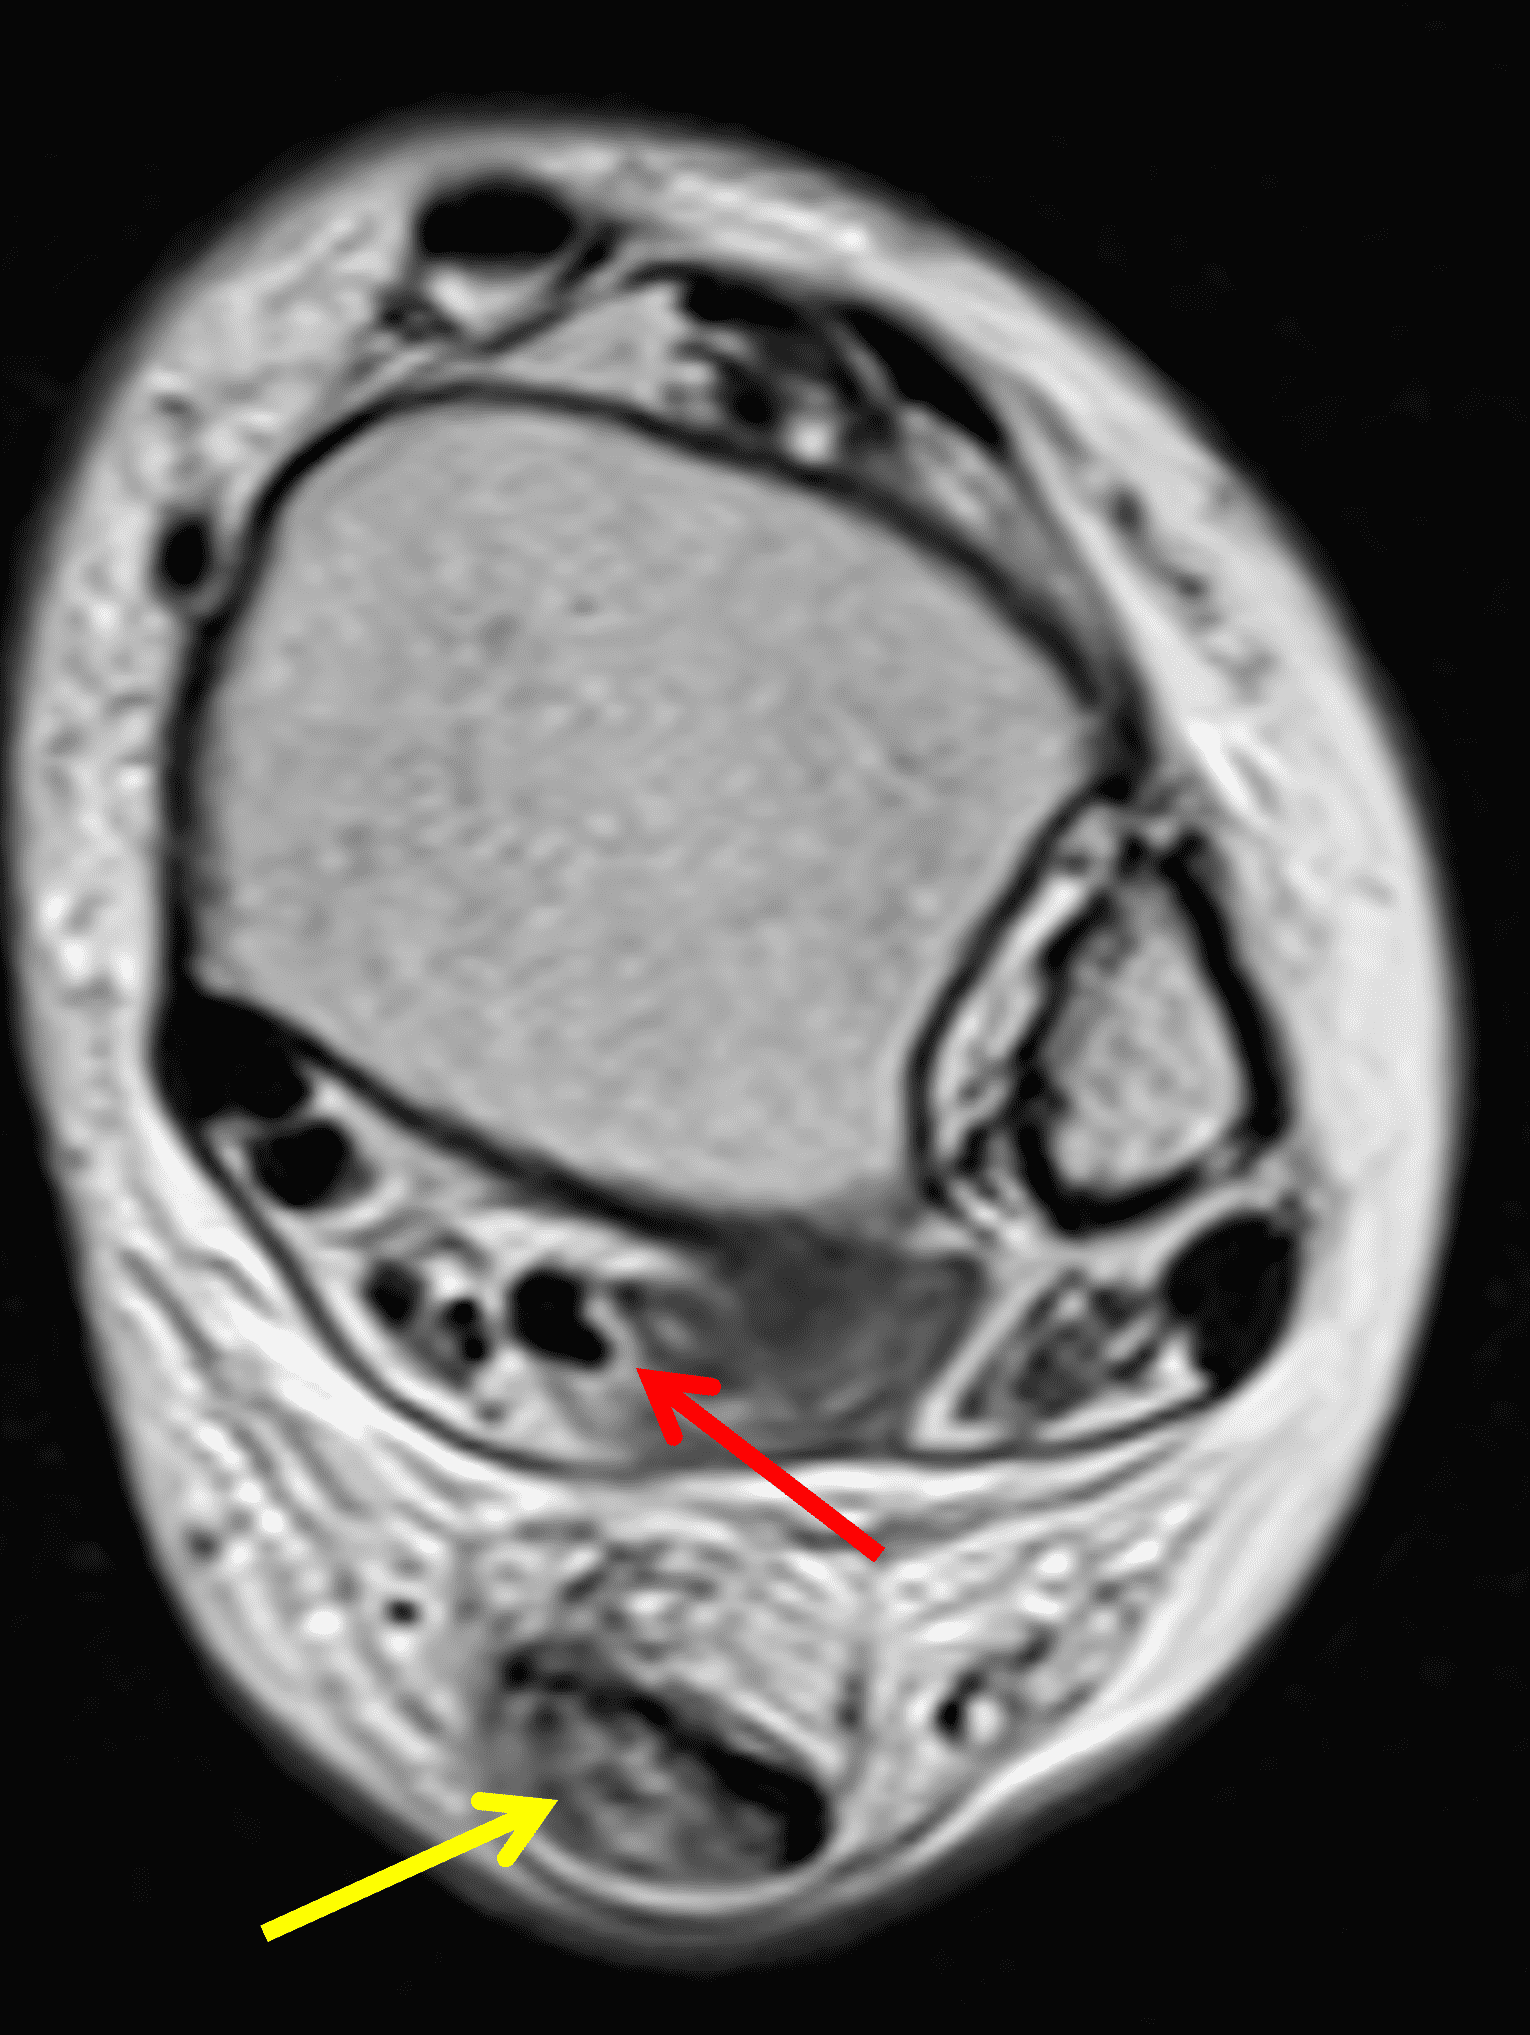

Figure 2: Complete Achilles tendon rupture. (2A) The lateral radiograph shows a thick and indistinct proximal Achilles tendon contour (arrows). (2B) A fat-suppressed T2-weighted image shows complete rupture of the tendon with a fluid-filled gap (yellow arrow) measuring 1.5 cm in length, located 10 cm cranial to the tendon insertion (blue arrow) and just distal to the edematous myotendinous junction (red arrow). The tear is superimposed on diffuse tendinosis. (2C) A sagittal T1-weighted image confirms the diffuse tendinosis. Fluid extends anteriorly into Kager’s fat pad (arrow) suggesting disruption of the anterior paratenon. (2D) A transverse fat-suppressed T2-weighted image through the proximal tendon shows no intact fibers (arrow), confirming the full-thickness rupture.